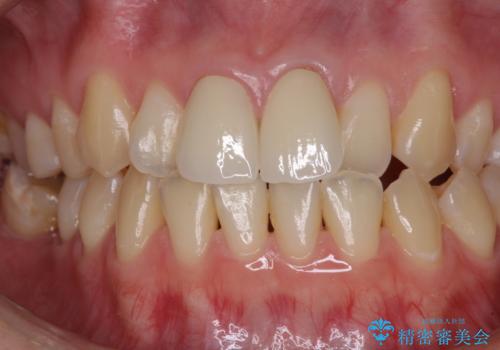

変色とともに、捻れていたことも気になっていたので、その両方を解決させることとしました。

2本同時に処置したことで、形や色調をそろえることができ、自然な口元になりました。